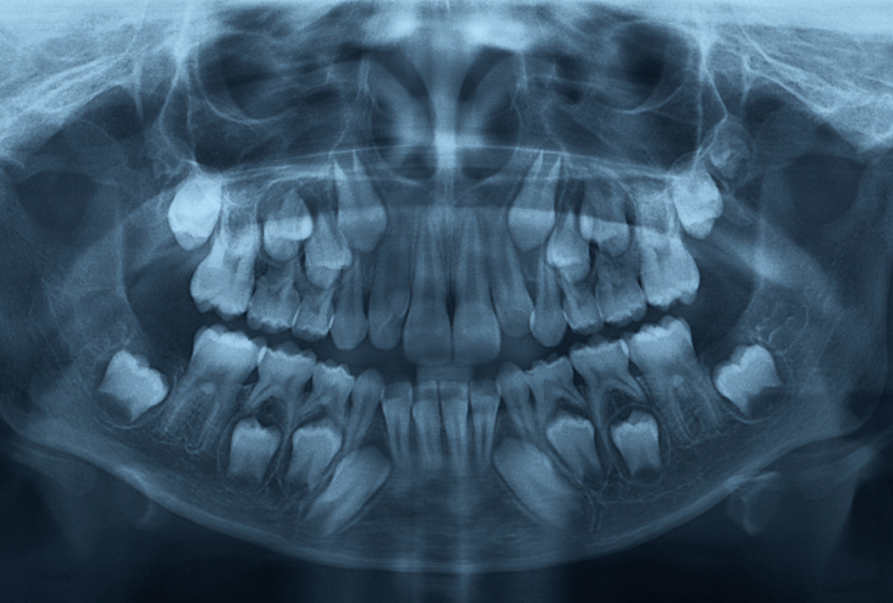

Radiology (Tooth X-ray or RVG)

At Podder Dental Clinic, we utilize advanced radiology technology, including digital Tooth X-rays and RVG (RadioVisioGraphy), to provide accurate and efficient diagnostics. These high-resolution images allow us to detect issues such as cavities, bone loss, infections, and impacted teeth with precision, even in their earliest stages. RVG offers minimal radiation exposure and instant imaging, enabling quicker diagnosis and treatment planning. Our commitment to using modern, patient-friendly technology ensures you receive the safest and most effective care for your dental health.